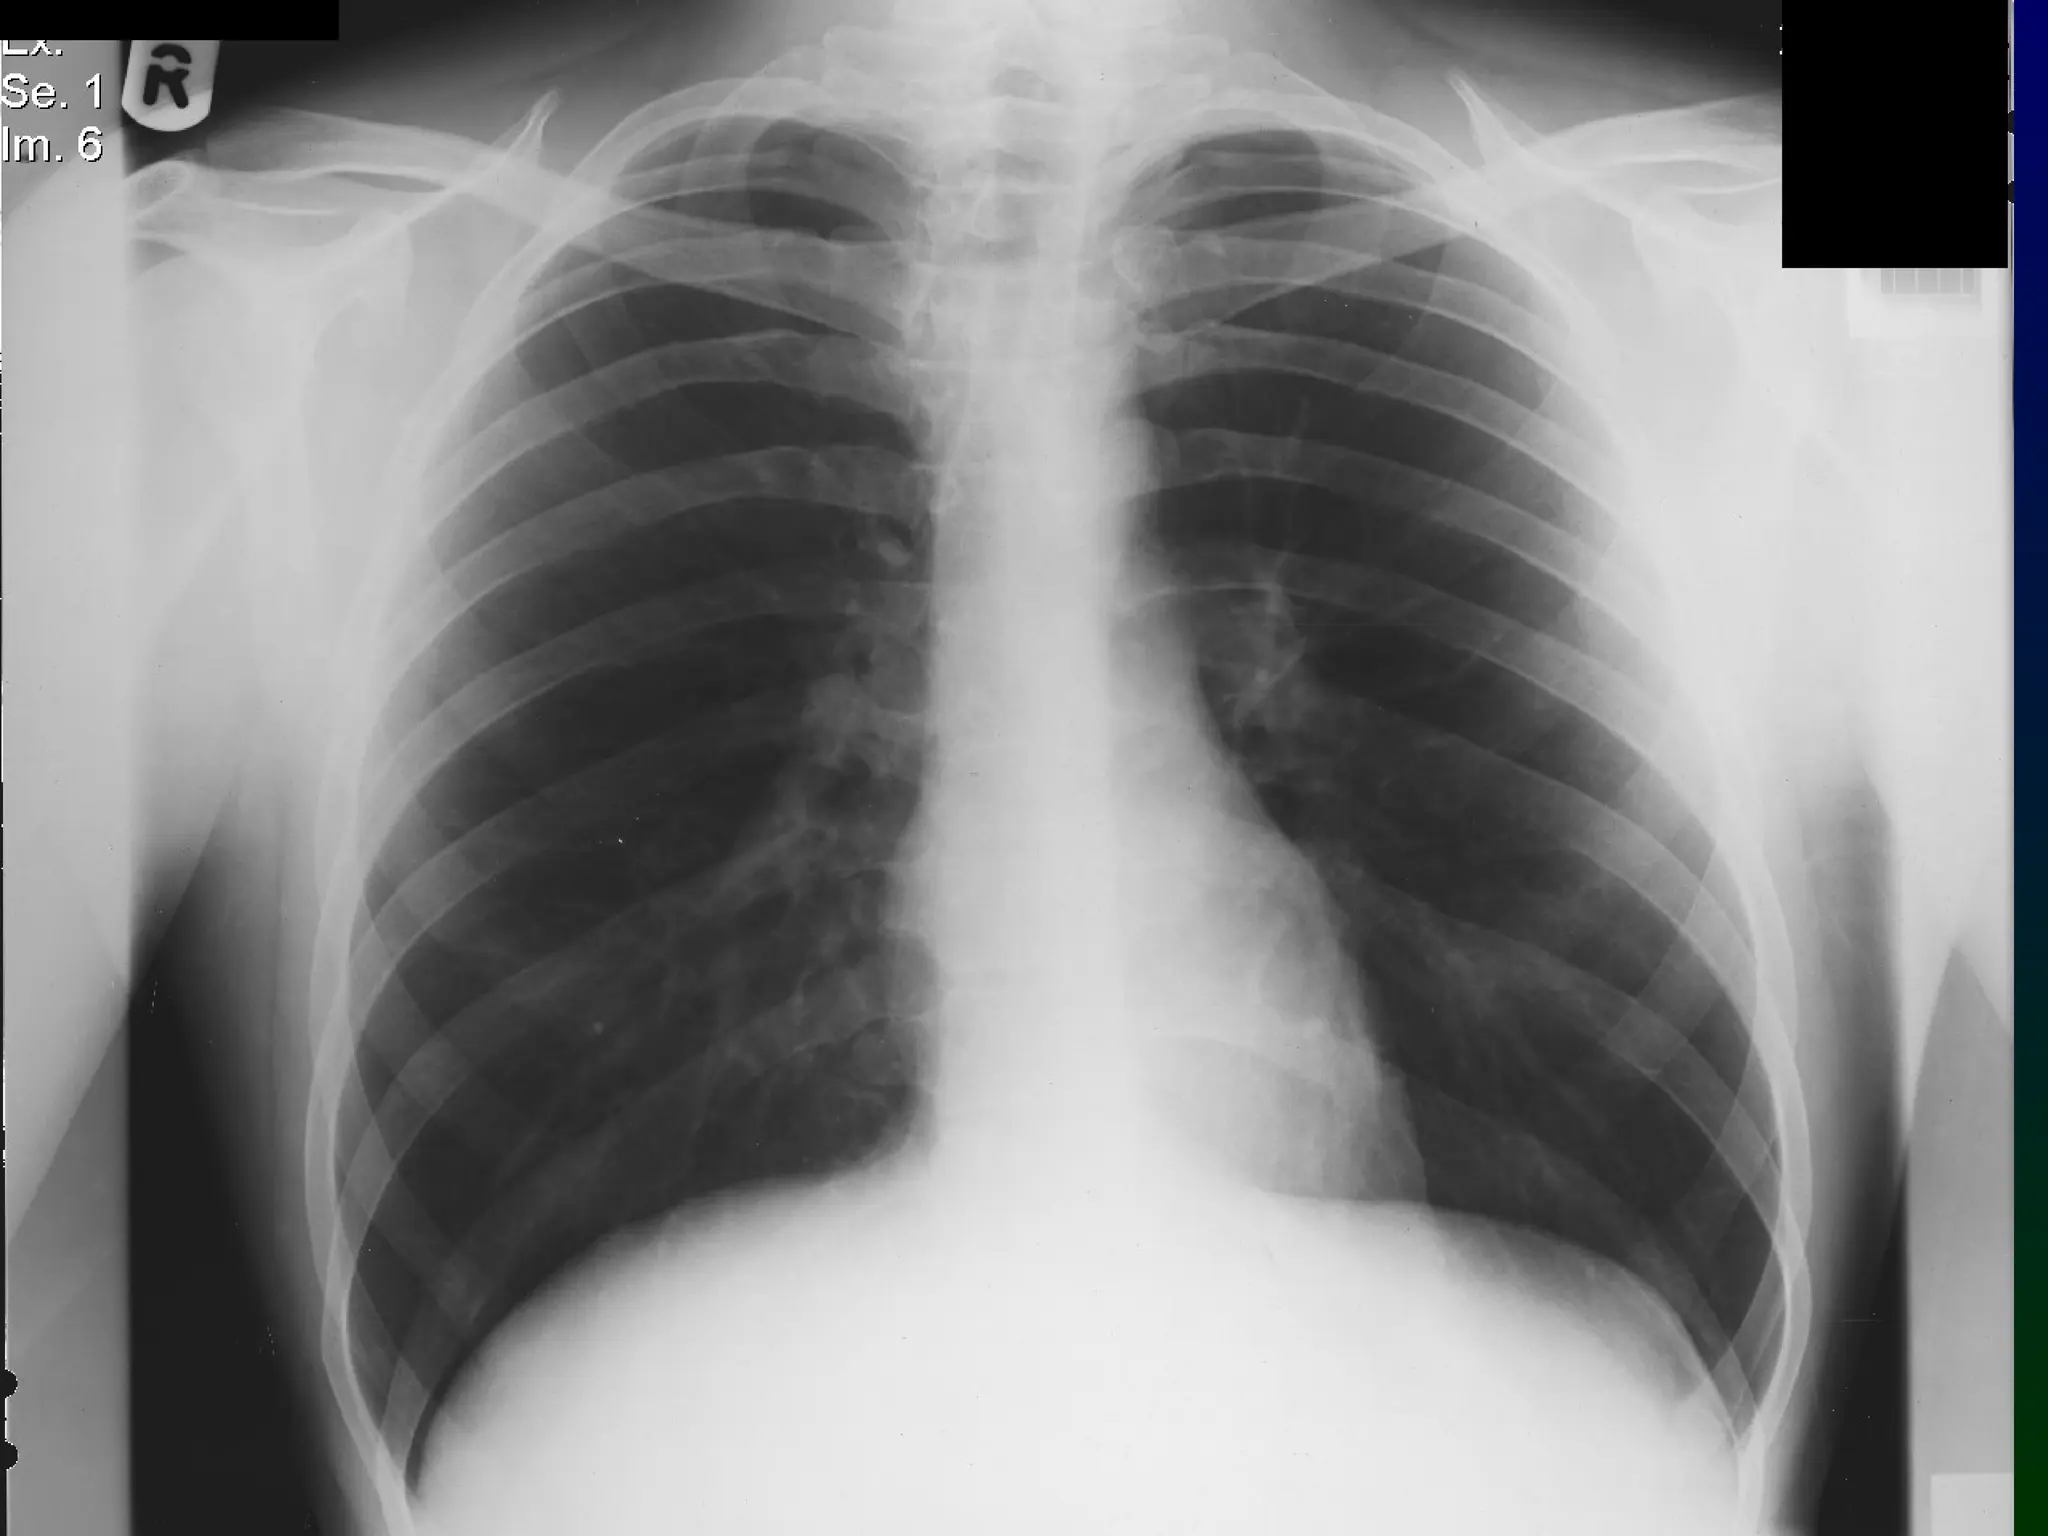

The CXR on the next slide is normal. How

would you interpret it?

How would you summarise this?

“This is an erect chest X-Ray of an adult male. The

heart is not enlarged, the mediastinal contours are

normal and the lungs are clear”